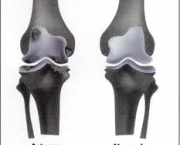

O desenvolvimento dessa doença se dá pelo desgaste das cartilagens responsáveis por revestir as extremidades ósseas de forma a causar muita dor e até mesmo deformações. A incidência de Artrose no Joelho é bastante comum porque as articulações do joelho estão dentre as articulações mais afetadas pela sobrecarga de peso.

O principal sintoma que a Artrose no Joelho apresenta é a dor constante, essa dor tende a piorar quando é feito um grande esforço ou mesmo com a rigidez matinal das articulações comprometidas. O indivíduo pode ter alguma dificuldade em apoiar o seu peso no joelho que sofre com o problema.

Outro sintoma bastante significativo desse problema nos joelhos é sentir um tipo de crepitação quando faz algum movimento com os joelhos. Devido ao crescimento de ossos ao redor do joelho o indivíduo sente que o joelho está inchado. Quando uma pessoa começa a sentir além de dores nos joelhos perda de sua função (de aguentar carga) deve procurar por um especialista.